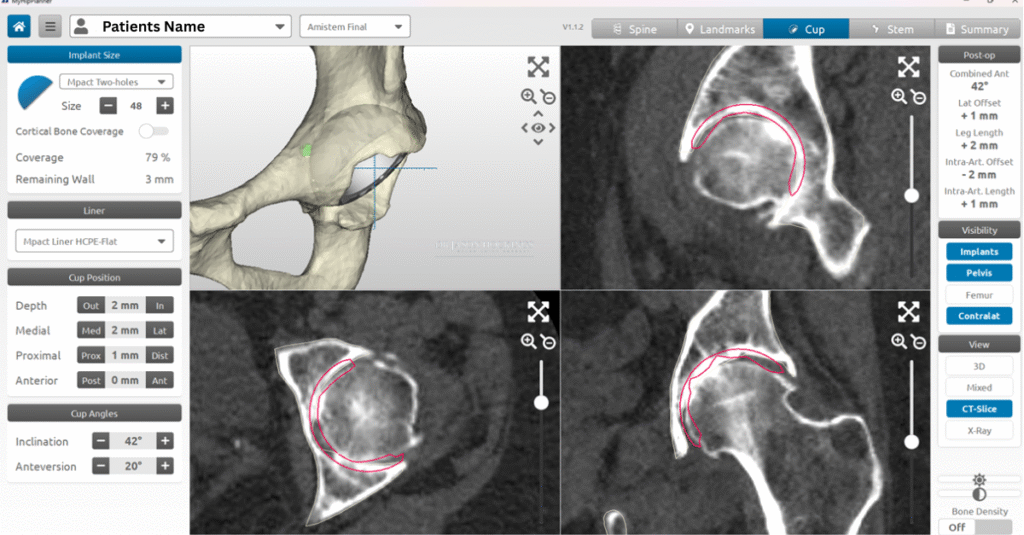

If total hip replacement is considered the most appropriate treatment, Dr Hockings will organise further diagnostic imaging to assist with surgical planning. You’ll be referred for a CT scan, which is used to create a 3D model of your hip using MyHip software for precise, patient-specific planning. Additional tests such as X-rays, blood tests, and general health checks may also be arranged as needed.

Once your CT scan has been completed, Dr Jason Hockings will use the data to develop a personalised 3D surgical plan using MyHip digital planning software. This system allows him to visualise your hip joint in three dimensions and assess your bone shape, joint orientation, and surrounding anatomy with precision.

Using this model, Dr Hockings can plan the size, position, and alignment of each implant component before surgery. This planning helps guide leg length, joint stability, and muscle balance while minimising the need for adjustments during the procedure.